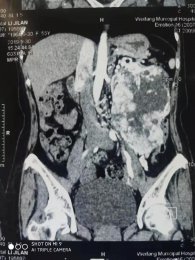

•   鏡益求精|我院泌尿外科腹腔鏡微創(chuàng)為患者切除左腎巨大腫瘤 日期:2019-10-18 16:41:25 點擊:1941 好評:35

隨著生活水平的提高,人民群眾對健康生活的要求不斷提高,許多人養(yǎng)成了定期查體的好習(xí)慣,通過查體往往能發(fā)現(xiàn)許多疾病的苗頭并加以預(yù)防。但也有部分健康意識較淡薄或工作繁忙的的朋友,沒有主動自覺查體的...